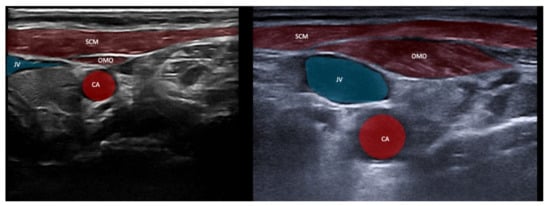

| Sternocleido-mastoid (SCM) | Contraversion of head and neck Ipsitilt of head and neck Anteflexion of head and neck with bilateral activation | + | ++ | Infrahyoid/supra-hyoid muscles, omohyoid, carotid artery, jugular vein | Dysphagia (particularly if injected bilaterally) |

3.4. Safety Issues and Imaging of Relevant Neighboring Structures